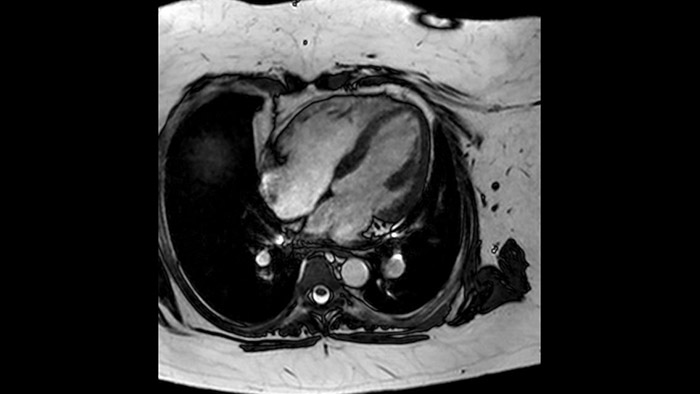

Combinando la smart-sync2 sviluppata dalla NORTHH MEDICAL (un sistema di Doppler a ultrasuoni compatibile con la MRI) con un sistema di RM Philips, abbiamo reso possibile la RM fetale cardiaca per fornire informazioni diagnostiche aggiuntive che possono aiutare nella diagnosi delle patologie cardiache congenite fetali, nel caso in cui l’ecocardiografia non sia sufficiente. Per saperne di più sullo smart-sync e scoprire cosa ne pensano i nostri clienti, clicca qui.